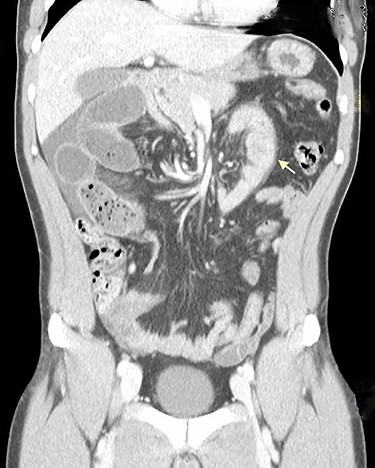

On physical examination, he was eupneic, hemodynamically stable and apyretic. His abdomen was soft, not distended, painless, with normal bowel sounds. Rectal examination showed an empty ampulla. Blood analysis revealed mild leukocytosis and little increase in C-reactive protein. Plain radiograph of the abdomen revealed dilated small bowel loops with air/fluid levels. Abdominal ultrasound revealed swollen intestinal loops on the right flank and interloop fluid. For further clarification, abdominal and pelvic computed tomography (CT) scan showed small bowel distension, air/fluid levels and free fluid (Fig. 1); signs of intestinal malrotation, with alteration of the normal topography of the duodenal arch (Fig. 2) and retrocecal position of terminal ileum (Fig. 3).

Coronal CT scan shows signs of intestinal malrotation, with alteration of the normal topography of the duodenal arch (arrow).